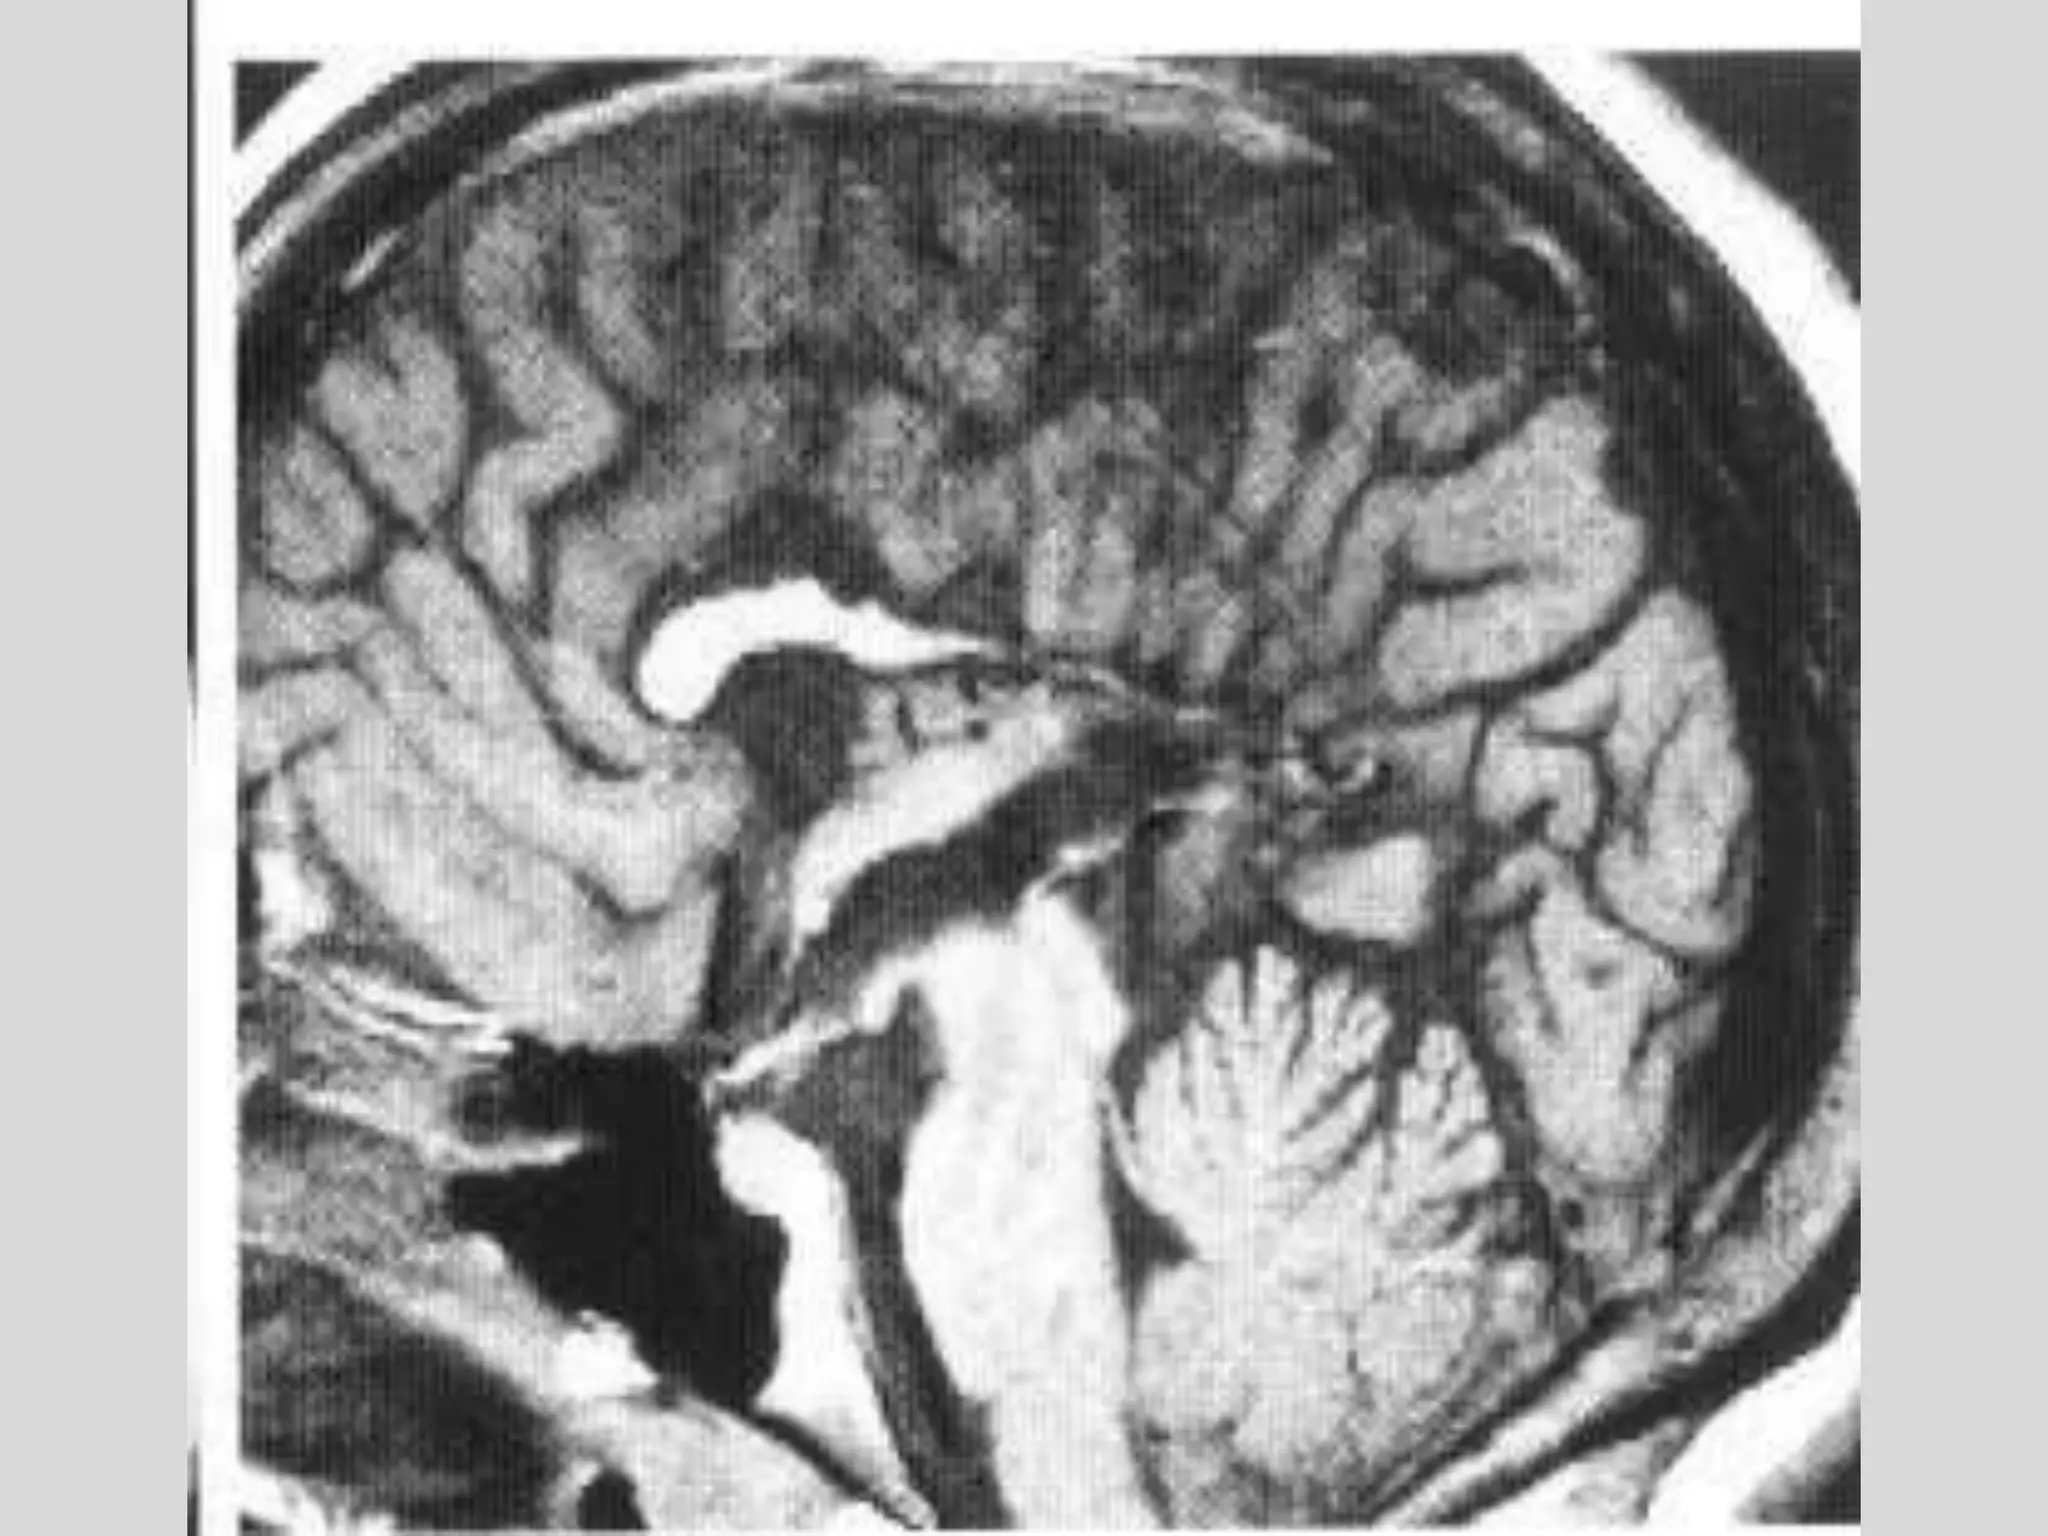

Brain tumors

• High-grade or malignant gliomas appear as

contrast-enhancing mass lesions, which arise

in white matter and are surrounded by edema

• Multifocal malignant gliomas are seen in ~ 5%

of patients.

• Low-grade gliomas typically are nonenhancing

lesions that diffusely infiltrate brain tissue and

may involve a large region of brain.

• Low-grade gliomas are usually best

appreciated on T2-weighted MRI scans.

Brain tumor

T2